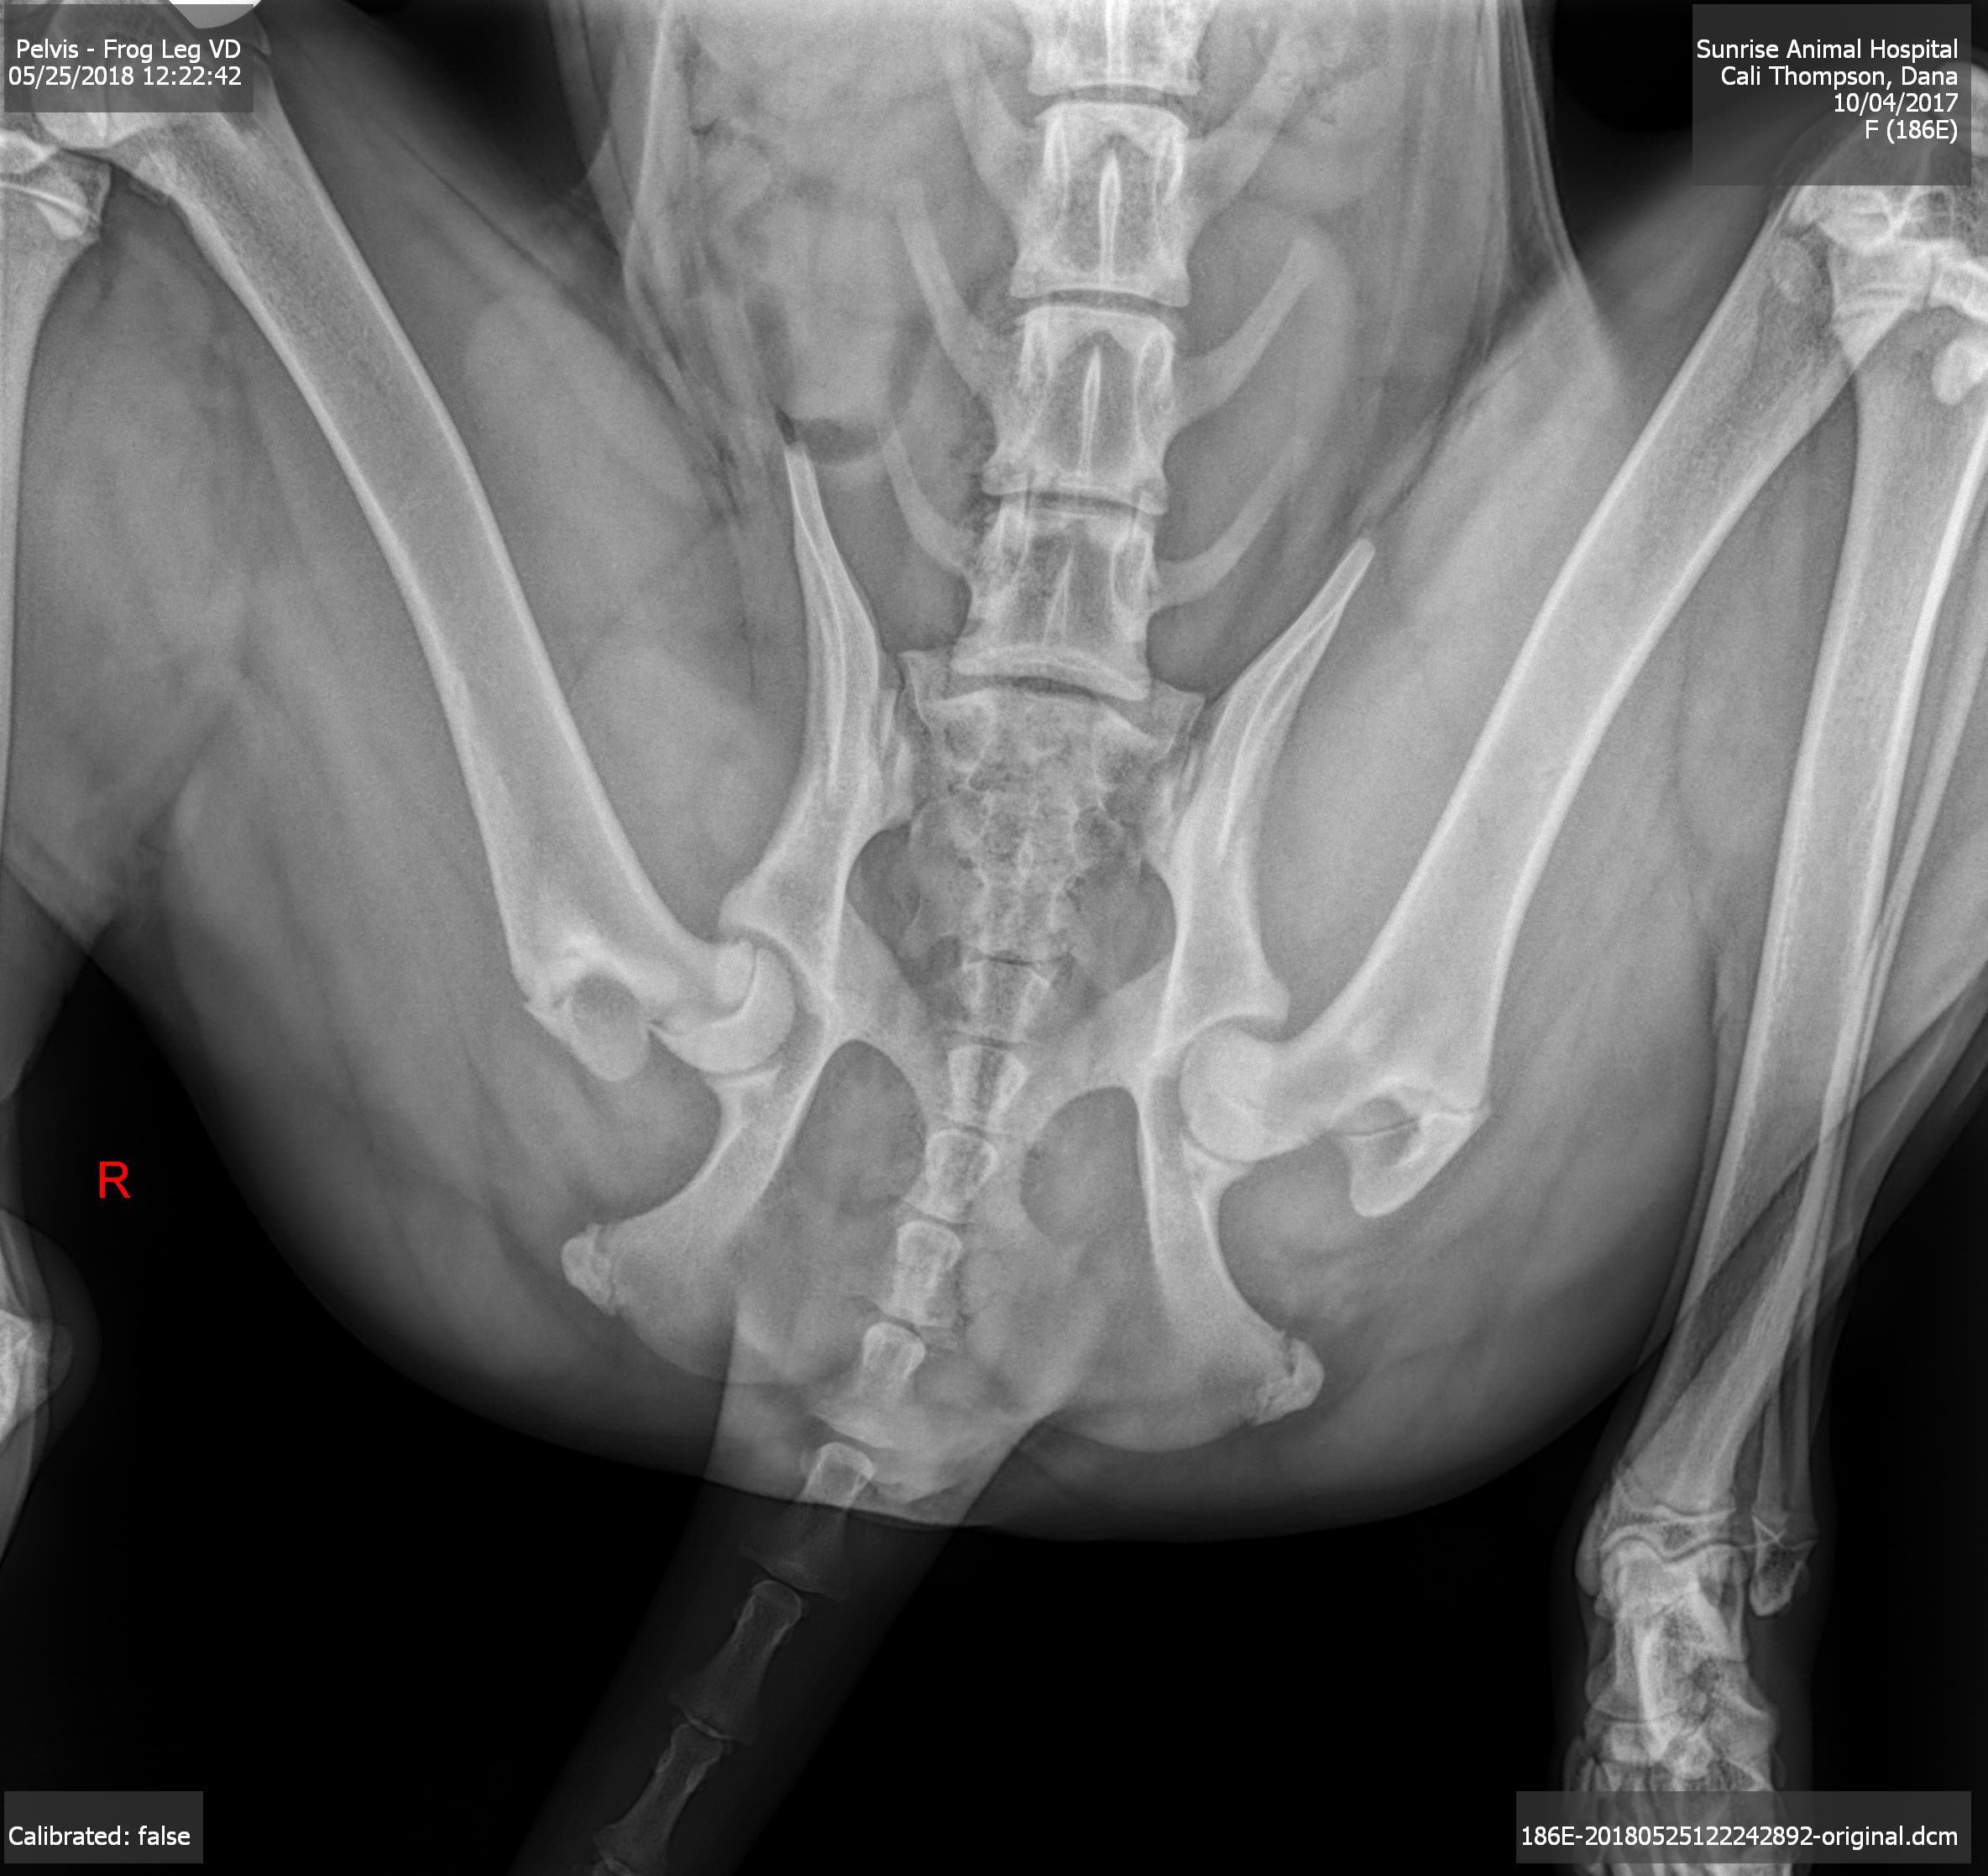

Pet's info: Dog | Bernese Mountain Dog | Female | spayed | 7 months and 24 days old | 50 lbs

Hi my 7 month old Bernese has been limping and not putting any weight on her back right leg. We went to the vet and had x-rays and were told her growth plate is dislocated. We were told she should rest for 5 weeks and where she is young and still growing it may re-fuse on its own. If it does not fuse by 5 weeks time, she may need surgery. Wondering about a second opinion and how serious this is? and how likely it will heal on its own?

The displacement here is very mild and it is likely with rest that it will fuse again but any joint injuries increase the risk of early onset arthritis and this will be more severe should it slip any further. An urgent review by a specialist orthopedic surgeon would be recommended to review all possible options and likely outcomes, especially in a giant breed such as Cali